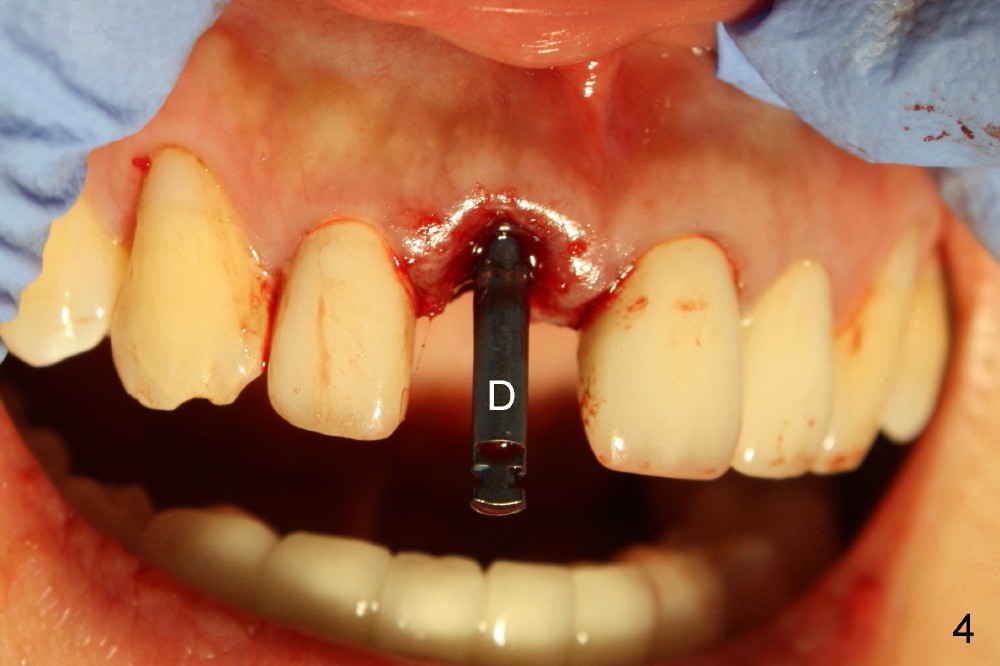

四十四岁女病人上颌中切牙突然断裂(图一:8),经过讨论,她同意植牙。由于根尖(图二黑线轮廓)上方骨头很多(箭头:鼻底),适合立刻植牙。牙根长度十一毫米左右,宽度约五毫米,准备植入直径五毫米植牙。拔牙后使用两毫米钻头,深度二十毫米(图三从颊侧牙龈缘算起),超过牙槽窝底部接近七毫米,所以植牙至少有七毫米新骨支持,将非常稳定。然后逐步使用2.5, 3.0, 和3.5毫米钻头,同一个深度,边钻边注意钻头(图四:D)近远中(图四)以及颊舌侧(图五)方向。